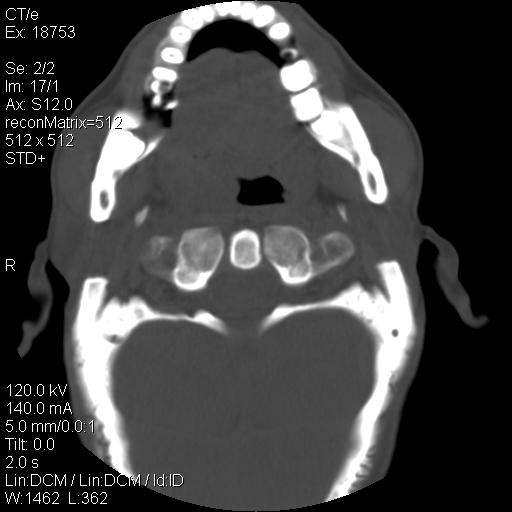

标题: CT21693:男 58岁 右侧咽部疼她2天余 PE:右侧扁桃体肿大 压痛 [打印本页]

标题: CT21693:男 58岁 右侧咽部疼她2天余 PE:右侧扁桃体肿大 压痛

右化脓性扁桃体炎症伴咽后壁脓肿形成.

喉部新生物,喉癌可能大,建议喉镜取组织活检。

考虑感染性病变可能性大,建议抗炎治疗后复查,必要时鼻咽腔镜活检排除占位。